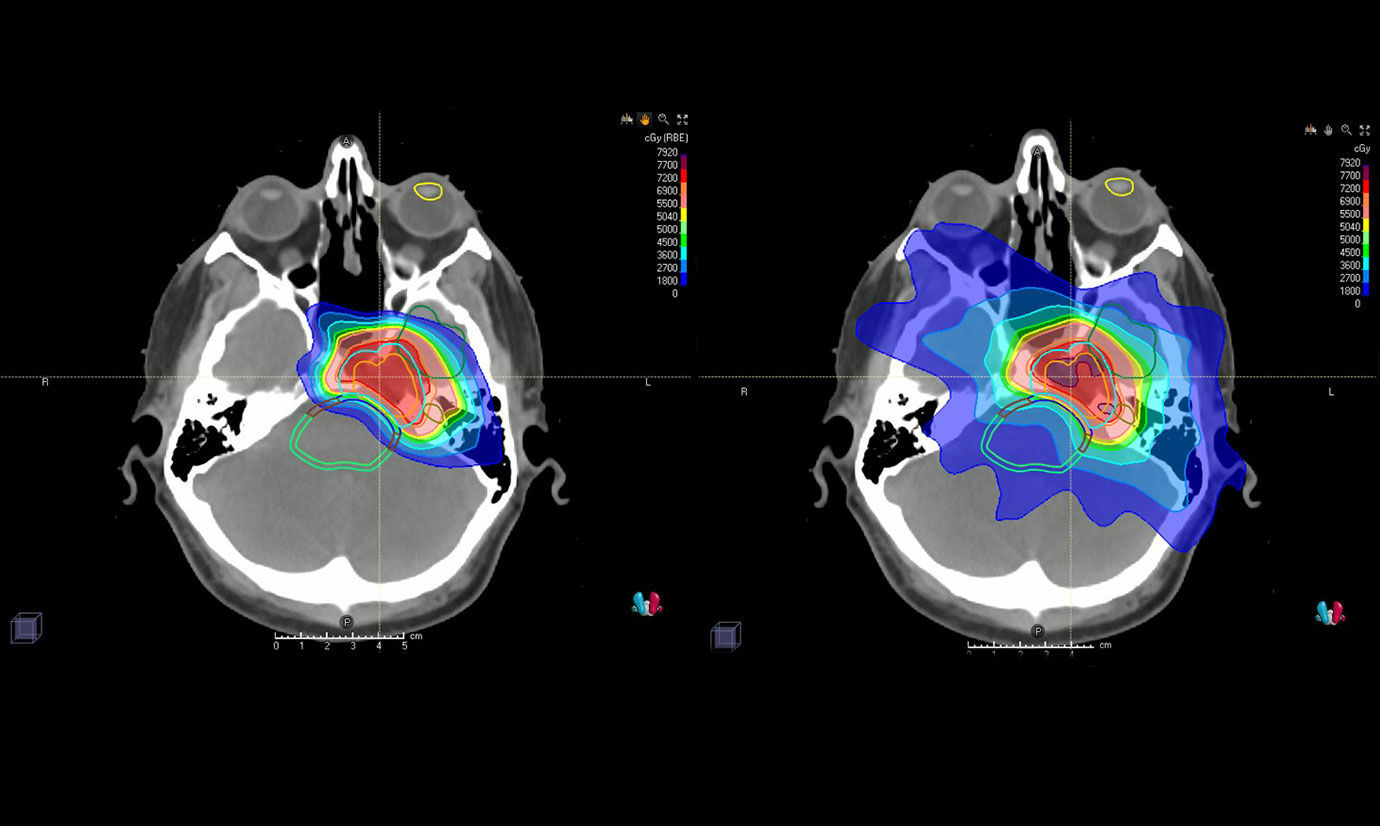

Proton therapy is a treatment option for some patients that can precisely target tumors while minimizing impact on surrounding tissues. In 1991, loma linda medical center Also, the proton therapy is an excellent treatment of tumors in children, since it has a minimal negative effect on the immature, sensitive tissues of the child’s body.

The ability to target proton therapy with laser precision on a minute area of the body enables physicians to attack malignant tumors, while limiting risk to surrounding healthy brain tissue and sensitive nerves in the spine. Benign brain tumors need to be treated because they can cause serious health problems by pressing on sensitive areas of the brain. The protons can be controlled with greater precision to conform to.

The precise area of delivery offered by proton beam therapy may be beneficial for brain tumors in which even small amounts of damage to nearby normal tissues could have significant side effects. It is more targeted than conventional radiotherapy so does less damage to the healthy tissue around the tumour and in the rest of the brain. Proton therapy for brain tumors treating these tumors with conventional radiation therapy poses risks of neurological deficits, hormonal deficiencies and intellectual impairment.